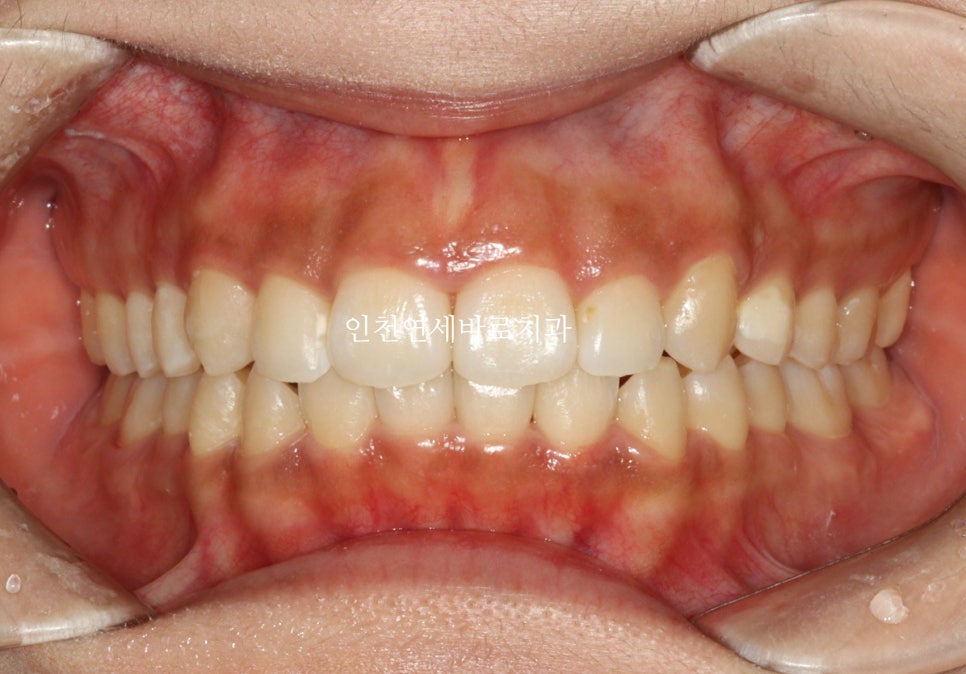

전후 비교입니다

전 후 교합의 비교입니다.

안정적으로 교합이 형성되었습니다

교정 끝난 직후의 사진이라 아주 약간은 제 마음에 안드는 부분이 있지만

11월말에 내원하시어 #비베라 제작을 할때 체크해보면 모두 해결이 되어있을 겁니다.